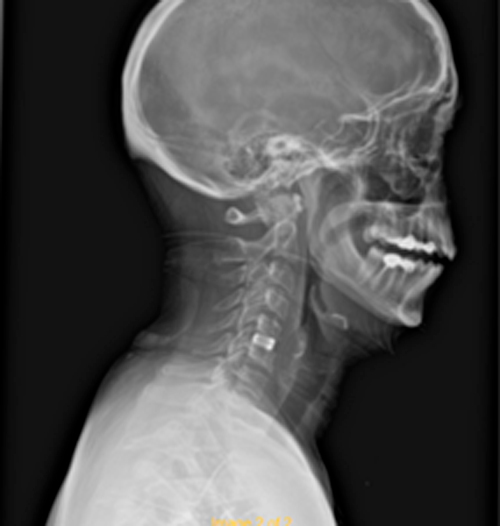

DIAGNOSI:

Ernia discale cervicale c5-c6

Risonanza magnetica cervicale pre-operatoria

Intervento chirurgico eseguito:

Microdiscectomia cervicale con approccio anteriore + introduzione di cage intersomatica cervicale

Radiografia cervicale post-operatoria